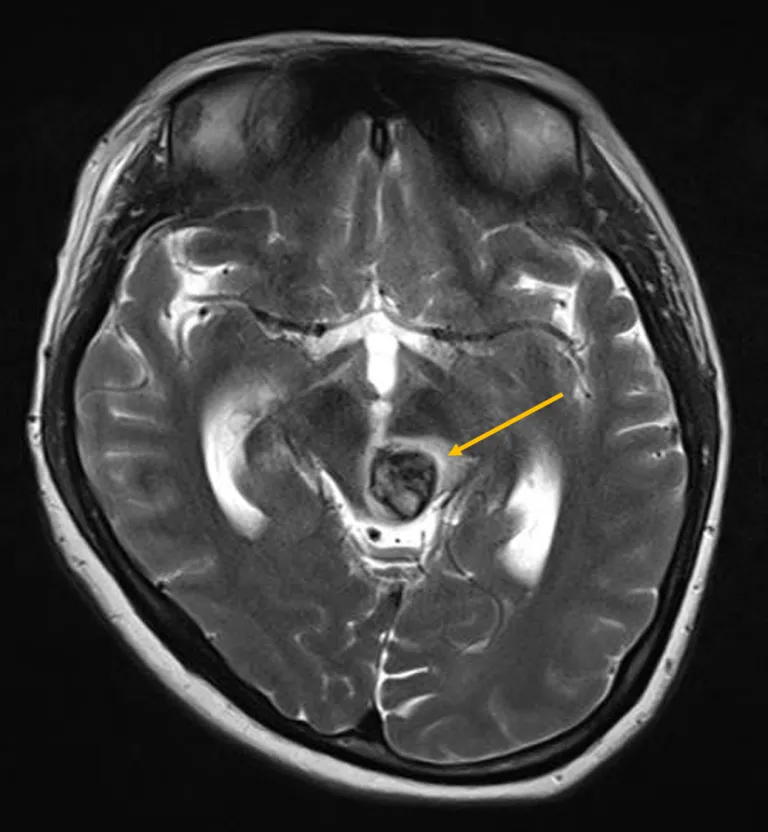

Kết quả chụp MRI cho thấy người bệnh có khối dị dạng mạch máu dạng hang rất hiếm gặp. Ảnh: BVCC